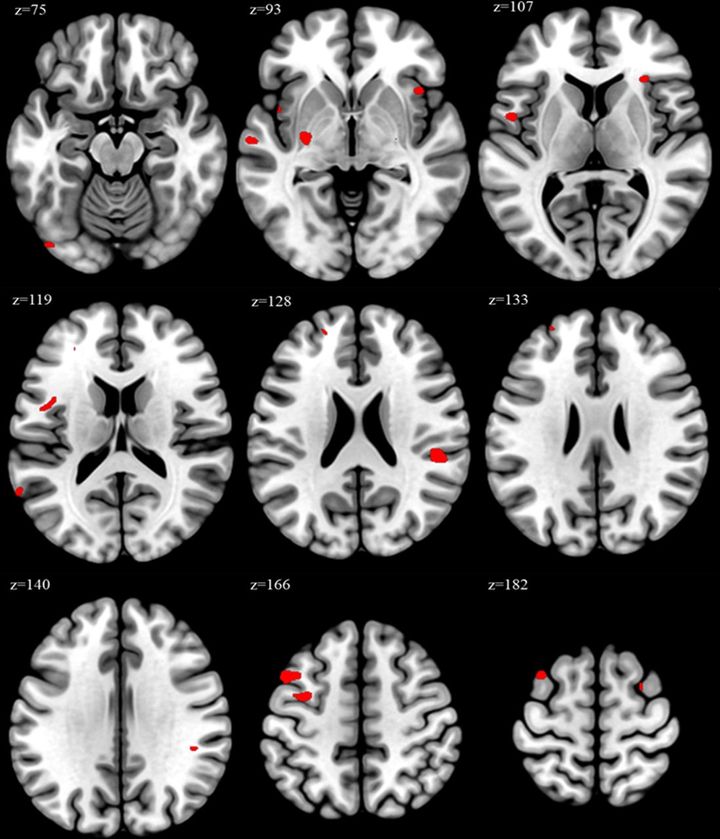

過労群の人では、通常労働群の人に比べて脳の一部の領域が大きくなっていました

具体的には、左中前頭回(left middle frontal gyrus)や島皮質(insula)などで、これは実行機能(executive function)や感情制御(emotional regulation)、ストレスへの反応に関わる領域です。

さらに、週の労働時間が長い人ほどこれらの領域の体積が大きいという相関もみられました。

VBM:ボクセルベース形態測定法で過労群と通常労働群の脳体積の違いが統計的に有意だった部位を示す脳画像マップ。赤いポイントが有意に体積が大きかった領域。/Credit:Wonpil Jang et al., Occupational and Environmental Medicine (2025)